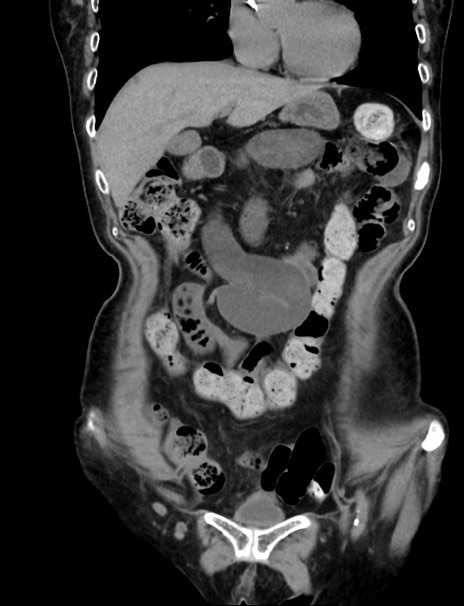

横断像

症例33(冠状断像)

【症例】70歳代 女性

【主訴】心窩部痛

【現病歴】延髄病変の精査・加療にて神経内科入院中。本日より心窩部痛あり。

【身体所見】右下腹部を中心に圧痛と反跳痛あり。

【データ】WBC 10900、CRP 0.02